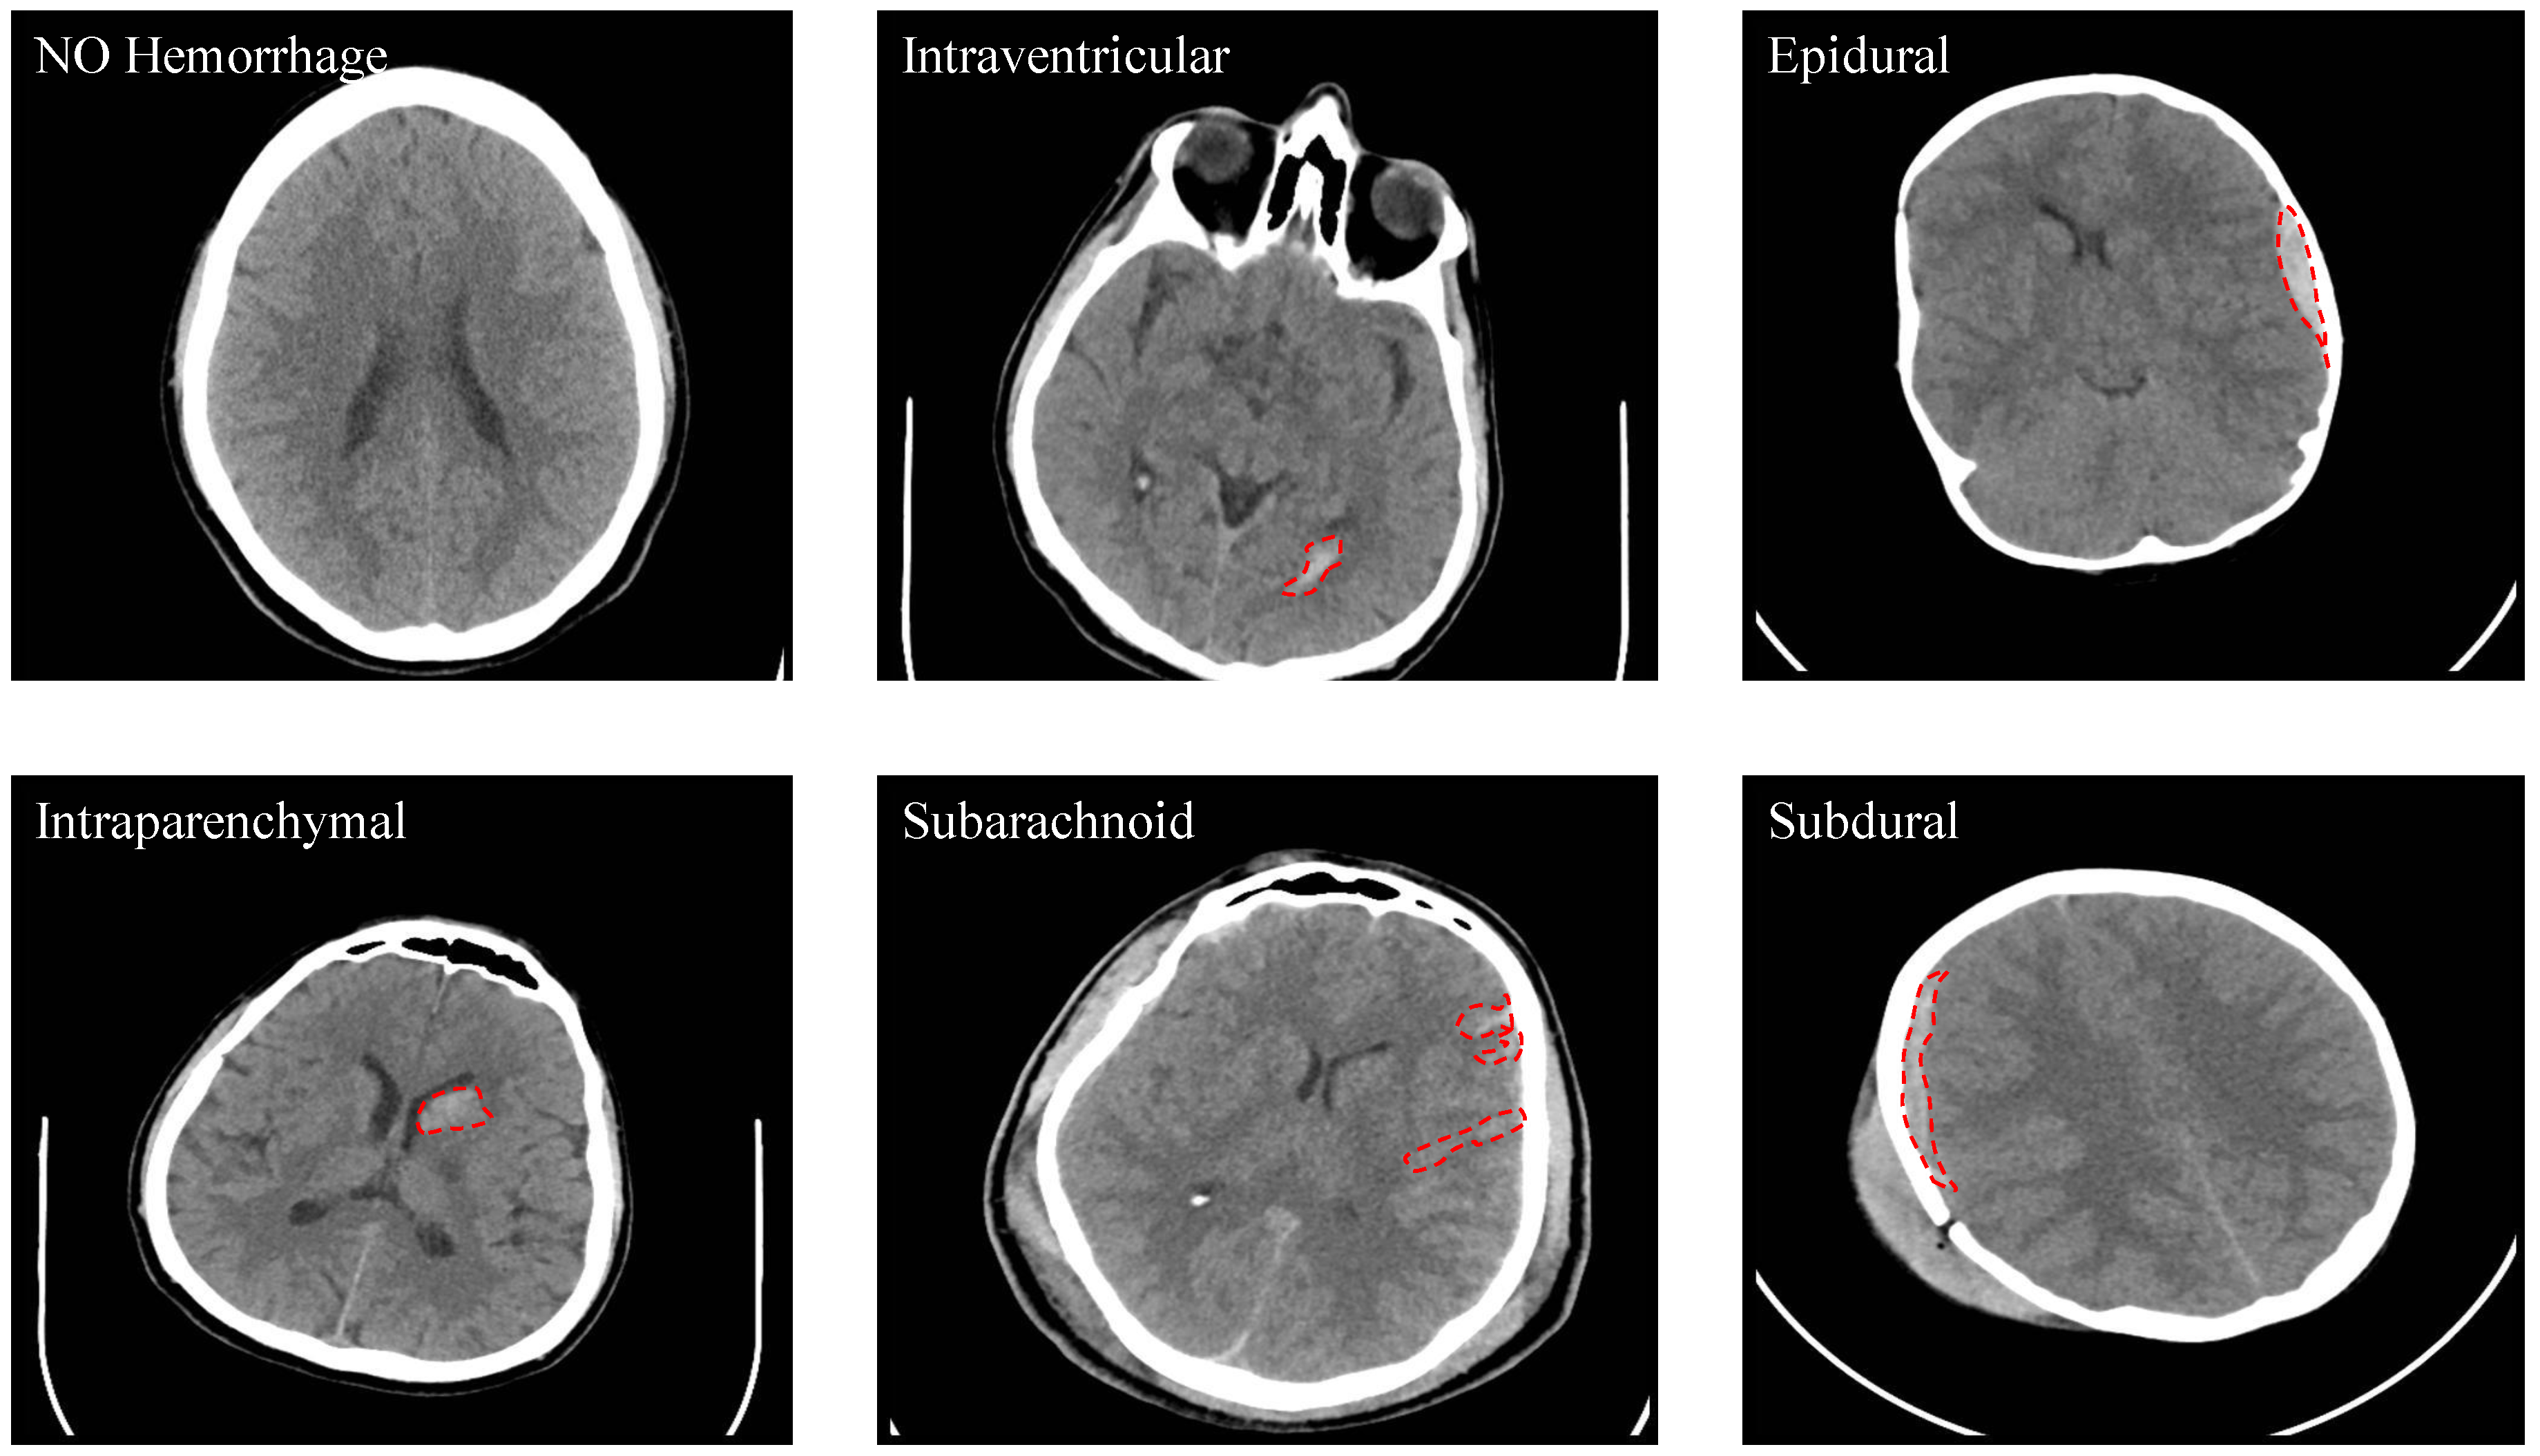

Out of the 82 subjects, 36 were diagnosed with an ICH with the following types: IVH, IPH, SAH, EDH, and SDH. See Figure 2 for some examples. One of the CT scans had a chronic ICH, and it was excluded from this study. Table 5 shows the number of slices with and without an ICH as well as the numbers with different ICH sub-types. It is important to note that the number of the CT slices for each ICH sub-type in this dataset is not balanced as the majority of the CT slices do not have an ICH. Besides that, the IVH was only diagnosed in five subjects and the SDH hemorrhage in only four subjects. Some slices were annotated with two or more ICH sub-types.

Figure 2.

Samples from the dataset that show the different types of ICH (Intraventricular (IVH), Intraparenchymal (IPH), Subarachnoid (SAH), Epidural (EDH) and Subdural (SDH)).